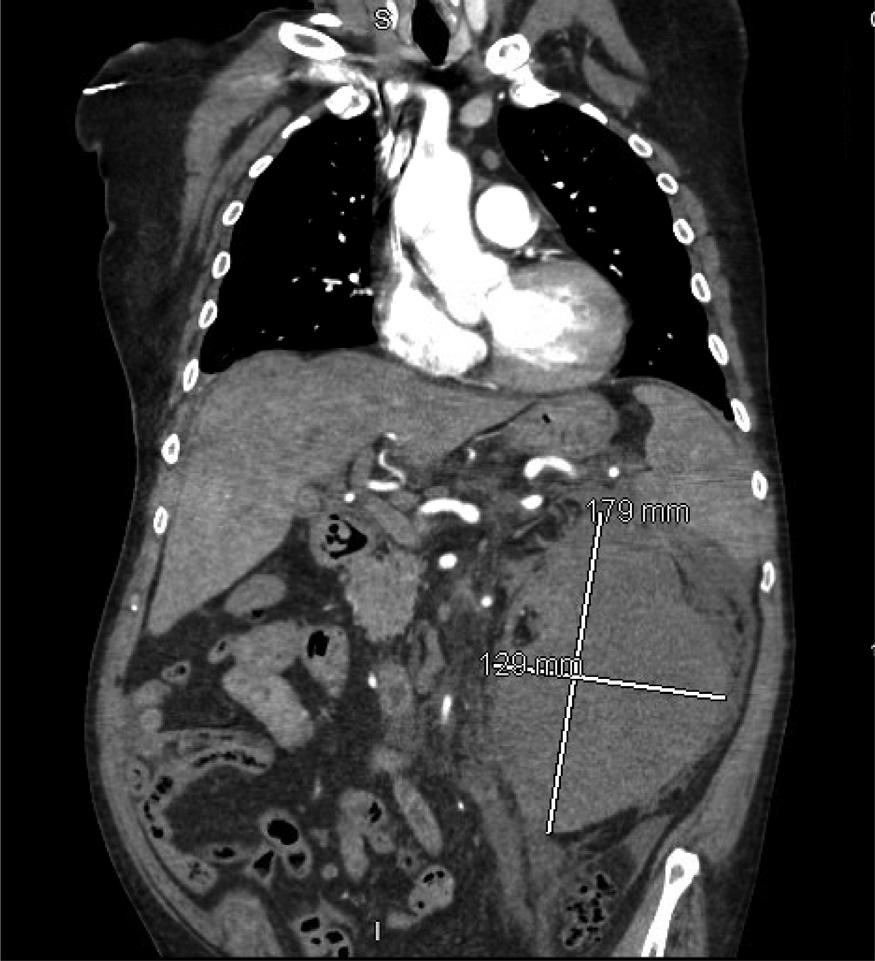

Emergentcomputedtomographyoftheabdomenand pelvisrevealedalargeleftretroperitonealandperitoneal hematomasecondarytoleftRAArupture,aswellasconcern fordevelopingsplenicinfarctsintheleftlowerrenalpole (Image).Thepatientwastakenemergentlytotheoperating room(OR)forexploratorylaparotomywithintwohoursof EDarrival.Sheunderwentsuprarenalcross-clampingwith repairoftheleftrenalarteryandligationofrenalvessels.She returnedtotheORtwodayslaterforleftnephrectomyand abdominalclosure.Shewasextubatedandtransferredtothe floor.Shewasdischargedhometwodayslaterin goodcondition.